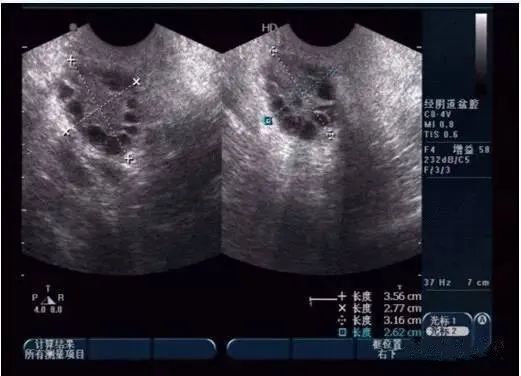

阴道B又称腔内B超,是用阴道探头对盆腔、子宫附件进行超声波的检查方式,可以观察子宫附件是否正常。

阴道B在临床应用很广,主要用于:早孕诊断、早期异位妊娠、子宫肌瘤、宫腔病变、滋养细胞肿瘤、盆腔肿块、炎症、胎头畸形、前置胎盘、卵泡监测等。